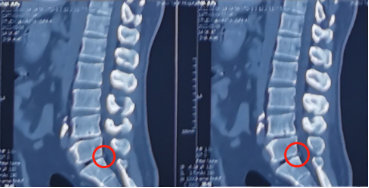

术前影像学资料

刘大姐来陕西冶金医院神经脊柱科了两次:第一次因为剧烈的腰痛和右腿疼痛,当时她疼得右边腿都抬不起来,走路只能扶墙走,平时活动离不开腰围,检查后发现她的腰5骶1处发生了突出,并严重地压迫、刺激到神经根。这种情况熊东主任建议刘大姐进行微创手术治疗,但是由于惧怕手术,她还是选择了保守治疗,并在神经脊柱科进行了康复理疗,症状缓解后出院。

而不到2个月,刘大姐的症状又再一次复发,并且更加严重,已经不能独立行走。这次,刘大姐前来主动要求进行手术,于是在完善术前各项检查后,熊东主任为她进行了椎间孔镜手术。